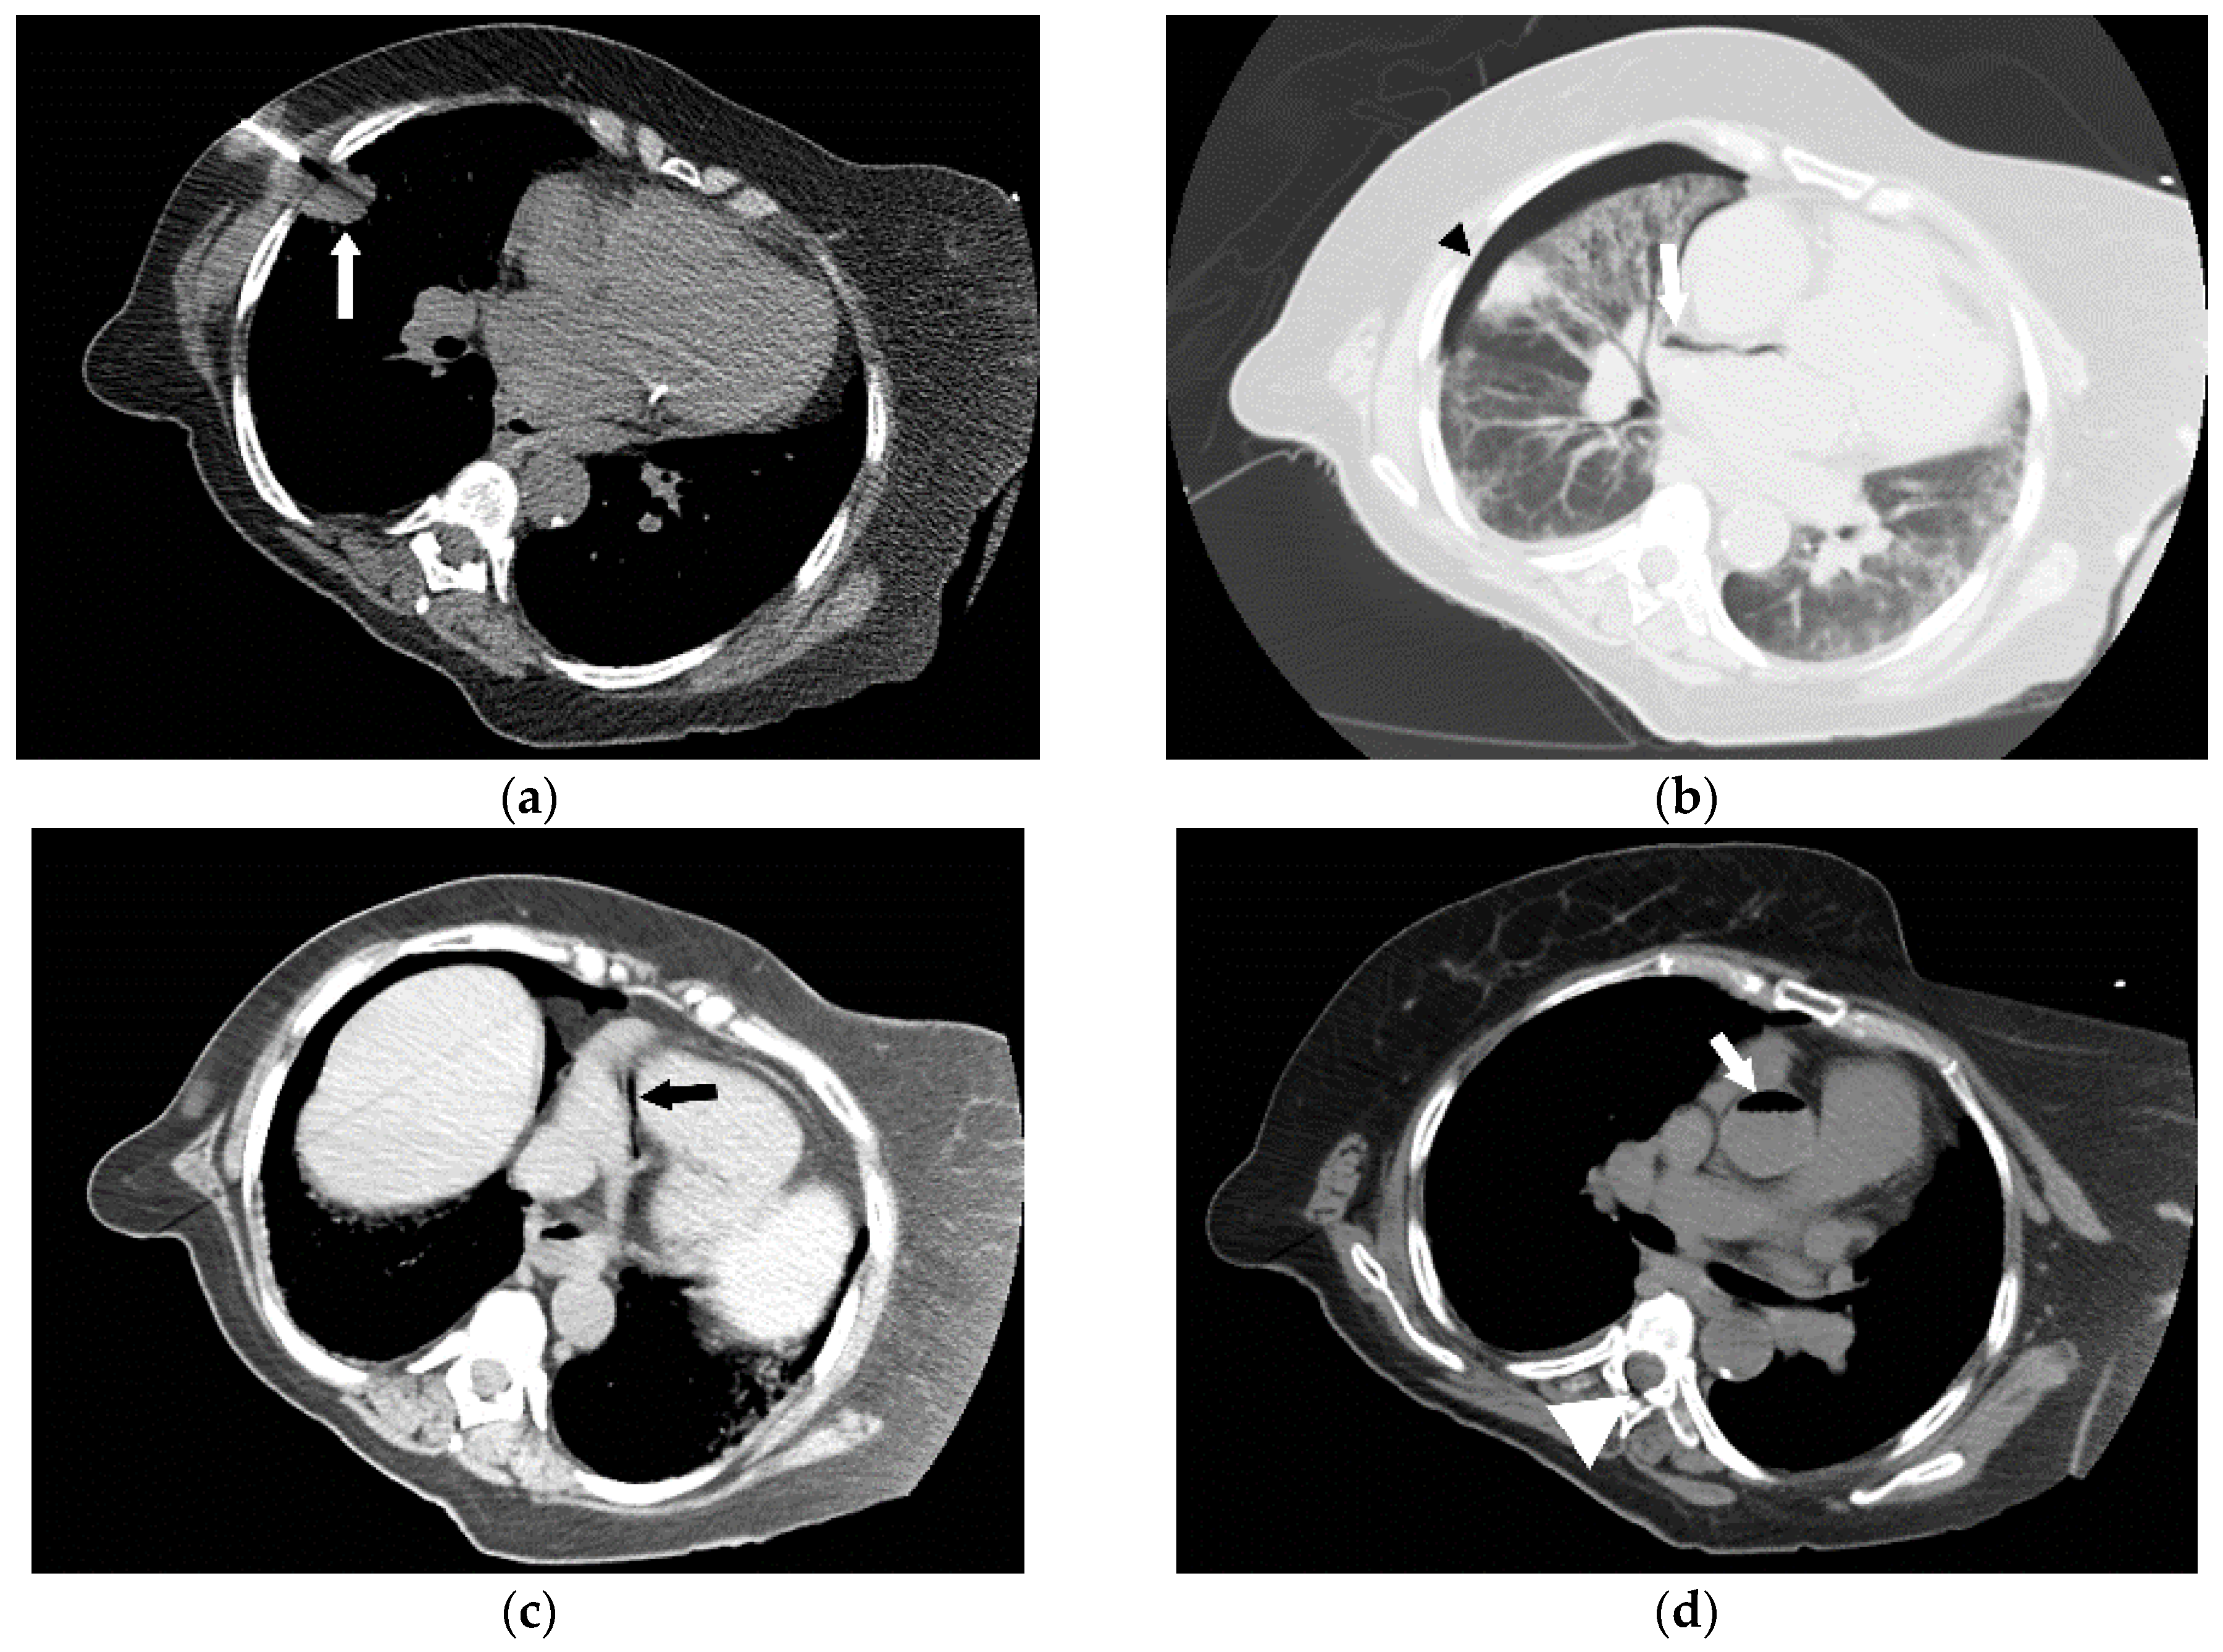

Figure 4.

Following the placement of right internal jugular tunneled Hickman line, a 76-year-old man developed an episode of desaturation, tachycardia, and non-responsiveness. Subsequently, an immediate CT of brain, neck and chest was performed and gas was found in the left cavernous sinus (a,b) and within a left parietal sulcus (c); it was felt to represent air in a vessel, possibly a pial vein. There was also a large amount of air surrounding the right internal jugular vein (d); with a partially visualized central venous catheter (*). A brain MRI was performed showing FLAIR hyperintensity in multiple regions (e) with evidence of restricted diffusion (f); and corresponding low signal (arrowheads) on the apparent diffusion coefficient (ADC) images (g). The patient received a single treatment of hyperbaric oxygen but died 8 days later.